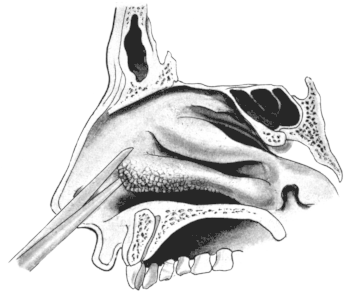

| 345. | Catheterizing the Sphenoidal Sinus | 654 |

| 210. | Passing the Eustachian Catheter | 365 |

| 211. | Passing the Eustachian Catheter | 365 |

| 212. | Passing the Eustachian Catheter | 366 |

| 213. | Passing the Eustachian Catheter | 366 |